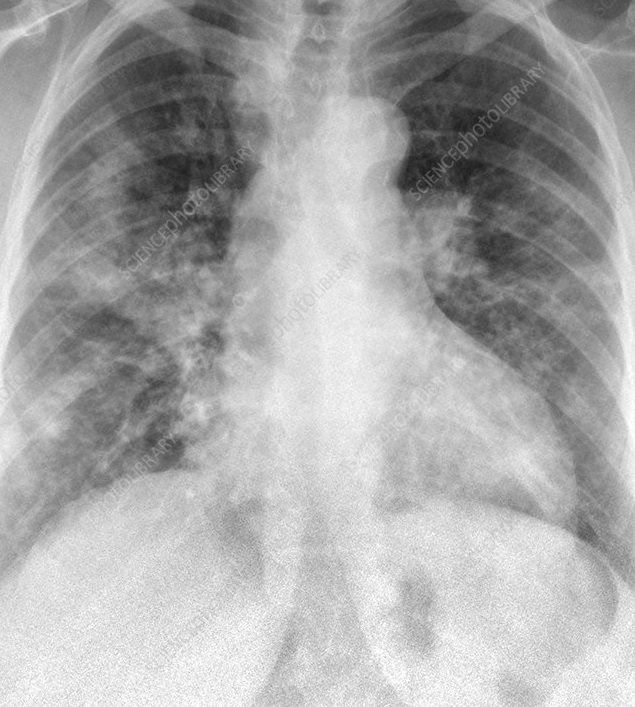

Figure 6 presents image examples for each class retrieved from the RYDLS-20 database. It is worth to mentioning that we have no further information concerning the CXR images with regarding the CXR machine used to take the image, as well as the origin, age and ethnicity of the people whose these images belong to.

Refer to caption

Figure 6: RYDLS-20 image samples.